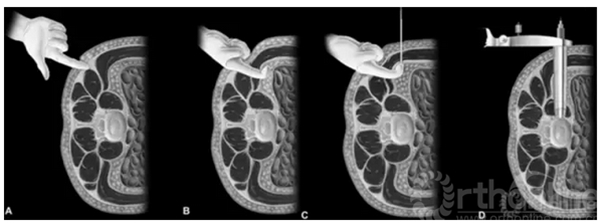

目前临床上进行侧入路(XLIF)腰椎椎间融合术,切口大约3-4cm。手术通常分离腹壁肌肉后,向前推开后腹膜,触及腰大肌并于椎间盘插入导针,逐层扩张并放入撑开器撑开,光源辅助下行间盘切除和融合。手术操作限于椎体中前部,避免了大血管相关并发症,且Cage覆盖椎体的两侧边缘。

XLIF示意